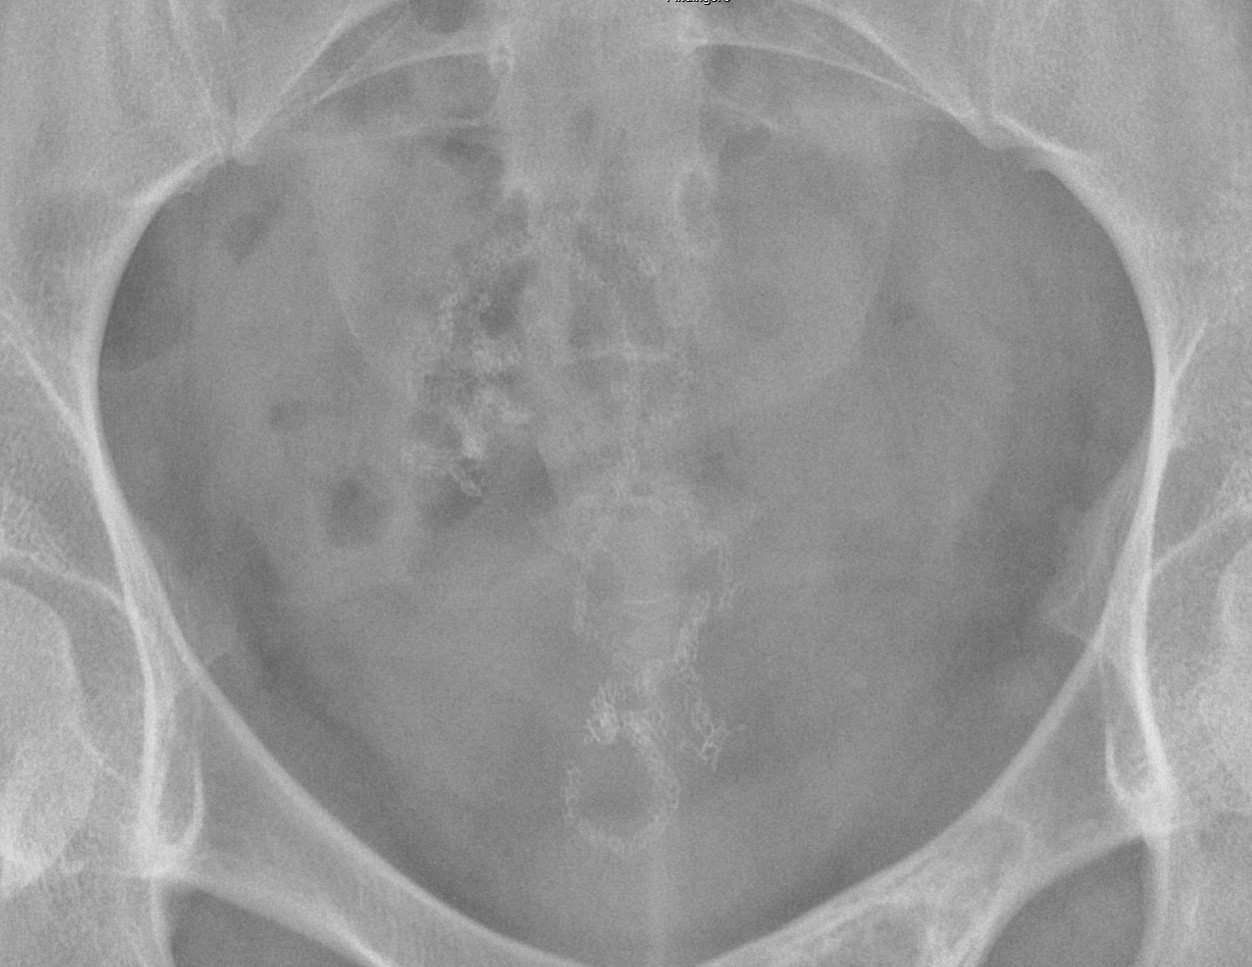

- The technologist will obtain a scout image. Assess the image for any possible contraindications such as pneumoperitoneum, evidence of ileus or obstruction, or residual contrast material

(key image 1).